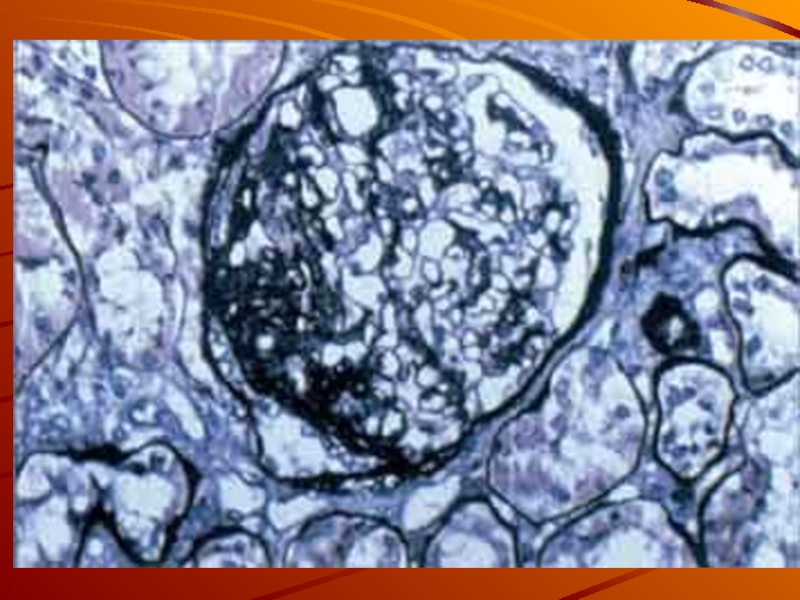

Механизм остро го диффузного гломерулонефрита